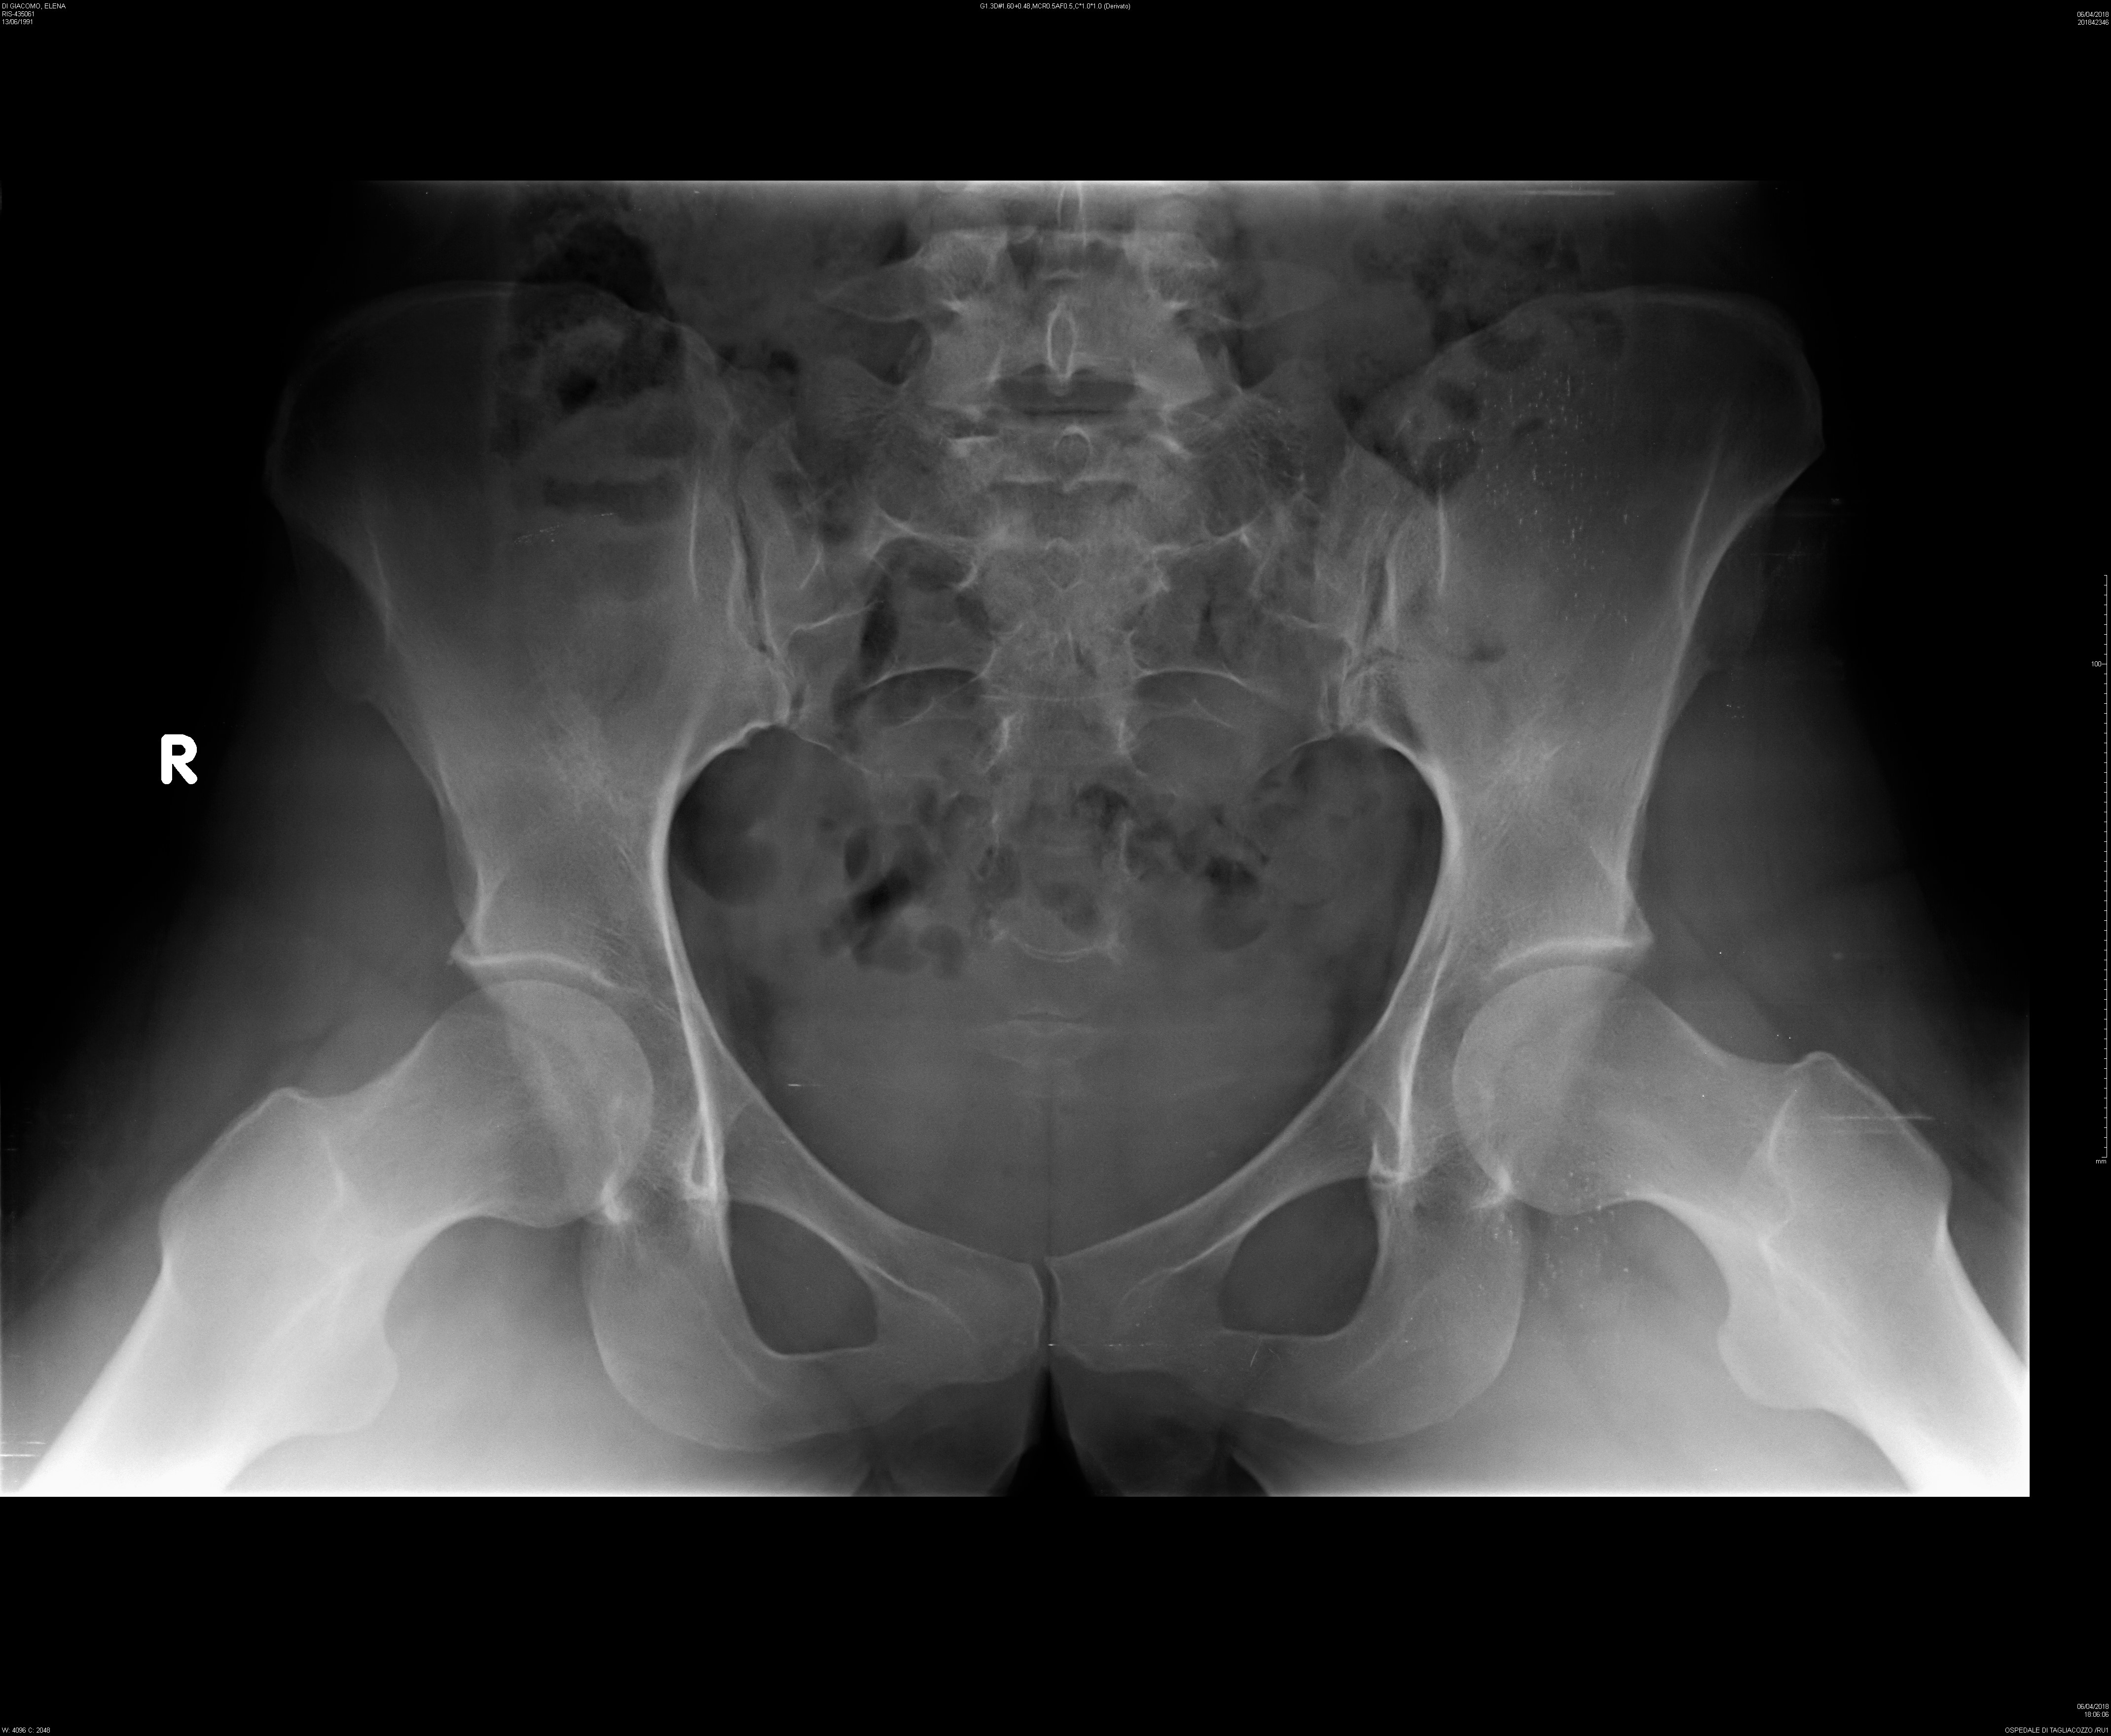

Salve, mi chiamo Elena, sono una ragazza di 27 anni e da circa un paio di anni ho un problema alla schiena. Il dolore è caratterizzato nella zona lombare , soprattutto nella parte sinistra, fino ad estendersi alla parte alta del gluteo sinistro.

Il medico, pensando fosse qualche infiammazione di qualche articolazione o altro, mi ha prescritto il ketoprofene per 10 giorni senza risulati. Così ho eseguito una lastra, le cito il risultato:

-Dismorfismo al passaggio LS per lombarizzazione di S1

-Riduzione d'ampiezza dello spazio discale L5-S1

-Rettilineizzata la lordosi lombare

-Non alterazioni morfostrutturali delle articolazioni coxofemorali

Il dolore/formicolio è persistente, delle volte durante qualche movimento rimango bloccata (soprattutto durante una camminata a passo sia normale che svelto), l'unico sollievo è stendermi supina, piegare le gambe e portarle fino al petto.